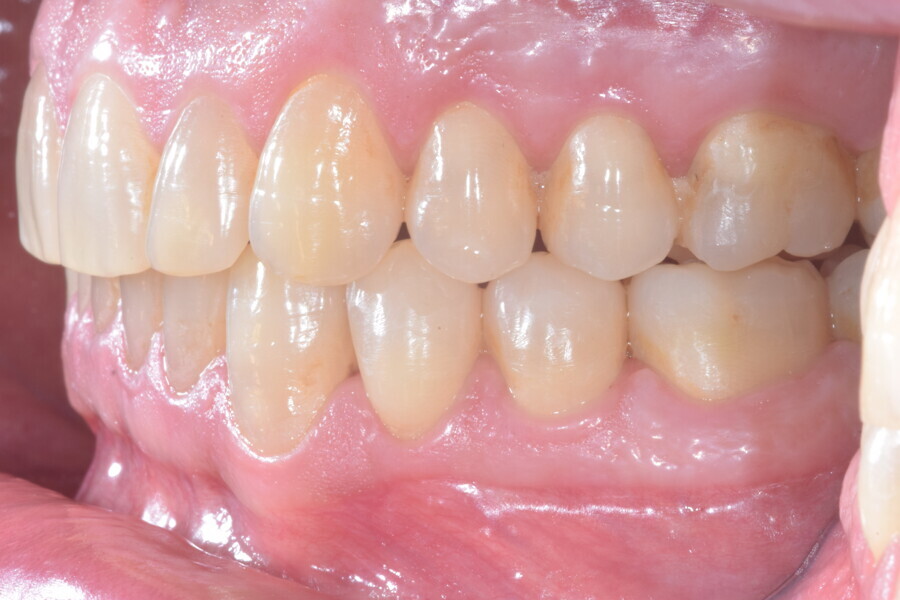

A 37-year-old male patient presented with the chief need for re establishing anterior alignment in both arches. Facial analysis showed a short face with a flat profile but proper chin projection (Figs. 9–12), and clinical examination revealed a skeletal Class I (ANB = 0.89°) and dental Class I malocclusion with severe deep bite (almost 100%), a deep curve of Spee, normal maxillary central incisor torque (Ui–FH = 110°), mild maxillary crowding and moderate mandibular crowding (Figs. 13–18). The deep bite components were represented in this patient by the severe skeletal condition of hypo divergent pattern (FMA = 14.24°) with normal maxillary and mandibular incisor inclination and decreased gonial angle (110.46°). Analysis of the cephalometric radiograph indicated a reduced lower anterior facial height, combined with a hypo-divergent pattern (Fig. 19). The only treatment option suggested was orthodontic treatment with aligners for deep bite correction with all the features described (bite ramps, pressure area, 3D curve of Spee levelling, Class II elastics and heavy occlusal contacts).

The digital treatment plan (ClinCheck) provided 12 aligners for the maxillary arch and 17 for the mandibular arch. The treatment objectives were focused on coupled vertical movements of posterior extrusion and anterior intrusion by means of bite ramps, providing for posterior disocclusion and anterior intrusion of mandibular teeth by means of extrusion attachments needed for mandibular arch levelling. The maxillary and mandibular incisors were proclined to level the upper and lower curve of Spee and to support the flat profile and the lips. Class II elastics were planned to support mandibular proclination and heavy posterior occlusal contacts with relative posterior extrusion. Lateral and posterior maxillary torque were planned to be close to 0°, to achieve wider arch design and ideal intercuspation. No digital over-engineering was planned in the set-up. Because of the age of the patient, the aligners were changed every ten days for a treatment time of less than six months. At the end of the first stage of aligners (Figs. 20–24), an additional stage was planned to improve molar intercuspation without elastics with a digital plan of five further aligners. This brought the total treatment time to 7.5 months since the additional aligners were changed every week.

At the end of the treatment, Class I canine and molar relationships were obtained, maxillary incisor inclination was slightly increased (Ui–FH = 112°), mandibular incisor inclination (IMPA = 97.09°) was fully corrected by means of proclination and the divergency was slightly increased (SN–GoGn = 27°) because of the relative posterior extrusion and use of Class II elastics—a small variation (1°), which is interesting considering the age of the patient (Figs. 25–35). A balanced smile arc was obtained with an ideal relationship between the maxillary incisors and lower lip, and torque control of the lateral and posterior segments generated a broader smile.